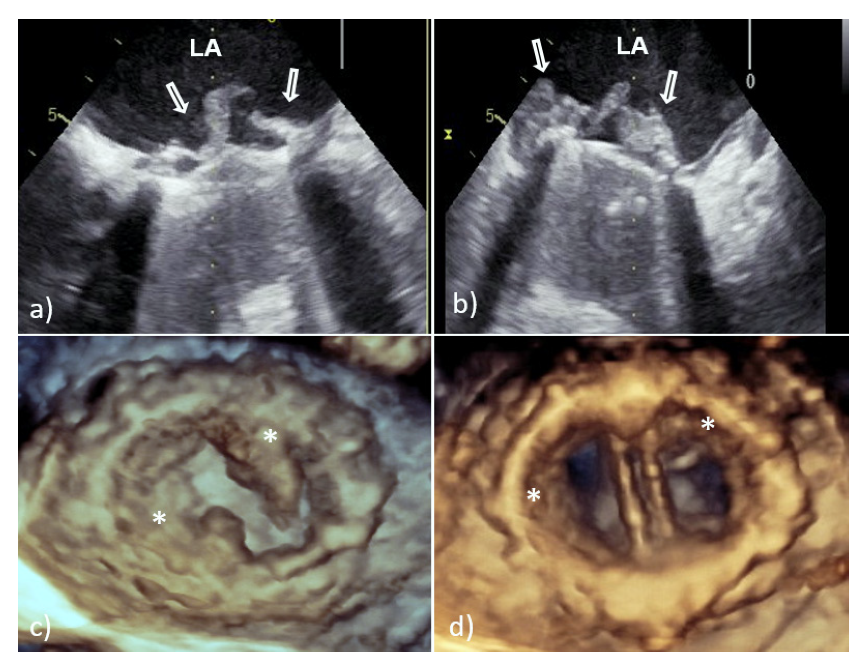

With TTE, it is more difficult to detect vegetation on PV than that involving native valves, because the highly echogenic suture ring and PV support structures can prevent detection of vegetation within the valve apparatus or its shadow [6,7]. Therefore, TEE should always be used if a diagnosis of PVE is suspected. In large series of PVE, TEE showed 86–94% sensitivity and 88–100% specificity for vegetation diagnosis; at the same time, the sensitivity of TTE was 36–69% [6,7]. Vegetative growth usually occurs as an abnormal echogenic mass with independent free movement attached to the atrial side of the mitral PV (Figure 2) [6,7].

However, vegetative growth can occur as thickening and irregularity of the normally smooth contour of the suture ring (Figure 2) or in the case of biological PVE as vegetation attached to the leaflets (Figure 3), sometimes with their consequent perforation or creation of a pseudoaneurysm [6,7].

Because the risk of embolism in patients with IE is related to the size, morphology, and mobility of vegetation, proper assessment of vegetation and monitoring of their size during antibiotic therapy have important prognostic implications [10,11]. Therefore, the accuracy and reproducibility of vegetation measurements is particularly important due to the greater effectiveness of early surgical interventions in patients with large mobile vegetation [10,11]. In this context, it is important that 2D TEE could underestimate vegetation compared to 3D TEE primarily due to limitations in selecting the maximum true diameter of irregular masses [10,11]. This shortcoming is solved by 3D TEE which allows infinite planes and volumetric reconstruction of masses (Figure 2). Because the main diameter of vegetation is important in the assessment of medical treatment response, as well as for setting a surgical indication in patients without other surgical indications, differences between the two TEE techniques in accuracy of vegetation measurements may have key therapeutic implications. In addition, 3D TEE allows better morphological classification of vegetation (e.g., filiform, sedentary, and clustered), and recognition of those associated with fragility and embolization (it seems that sedentary vegetation has the least embolic potential) [10,11]. Therefore, the main advancement of 3D TEE over 2D TEE is better assessment of vegetation characteristics—size, location, number, morphology, consistency, mobility, and relationship to valve structure—resulting in better prediction of potential embolic risk [10,11].

Figure 2. Transesophageal echocardiography of mechanical MVP endocarditis caused with Staphylococcus aureus: 2D TEE showed an extensive vegetation (white arrows) attached to the prosthetic ring and leaflets (a,b); 3D TEE showed voluminous vegetation (asterisks) affecting a whole circumference of sewing ring and MVP leaflets (c—in systole, d—in diastole). 2D TEE—two-dimensional transesophageal echocardiography; 3D TEE—three-dimensional transesophageal echocardiography; LA—left atrium; PVE—prosthetic valve endocarditis; and MVP—mitral valve prosthesis.